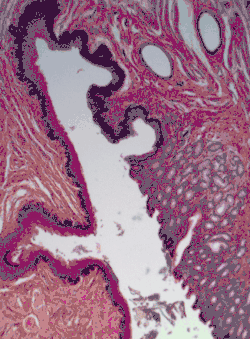

![]() Sección de la piel humana que muestra la superficie epitelial escamosa estratificada, conocida como Epidermis. La capa de queratina aquí se denomina "estrato córneo". | ||

Un epitelio escamoso estratificado o epitelio estratificado escamoso[1] consta de células epiteliales escamosas (aplanadas) dispuestas en capas sobre una Membrana basal. Solo una capa está en contacto con la membrana basal; las otras capas se adhieren entre sí para mantener la integridad estructural. Aunque este epitelio se conoce como escamoso, es posible que muchas células dentro de las capas no estén aplanadas; esto se debe a la convención de nombrar los epitelios según el tipo de célula en la superficie. En las capas más profundas, las células pueden ser columnares o cuboidales.[2] No hay espacios intercelulares. Este tipo de epitelio se adapta bien a las áreas del cuerpo sujetas a abrasión constante, ya que las capas más gruesas pueden desprenderse y reemplazarse secuencialmente antes de que quede expuesta la membrana basal. Forma la capa más externa de la piel y el revestimiento interno de la boca, el esófago y la vagina.[3]

En la epidermis de la piel de mamíferos, reptiles y aves, la capa de queratina en la capa externa de la superficie epitelial escamosa estratificada se denomina estrato córneo. El estrato córneo está formado por células escamosas que están queratinizadas y muertas. Estos se desprenden periódicamente.